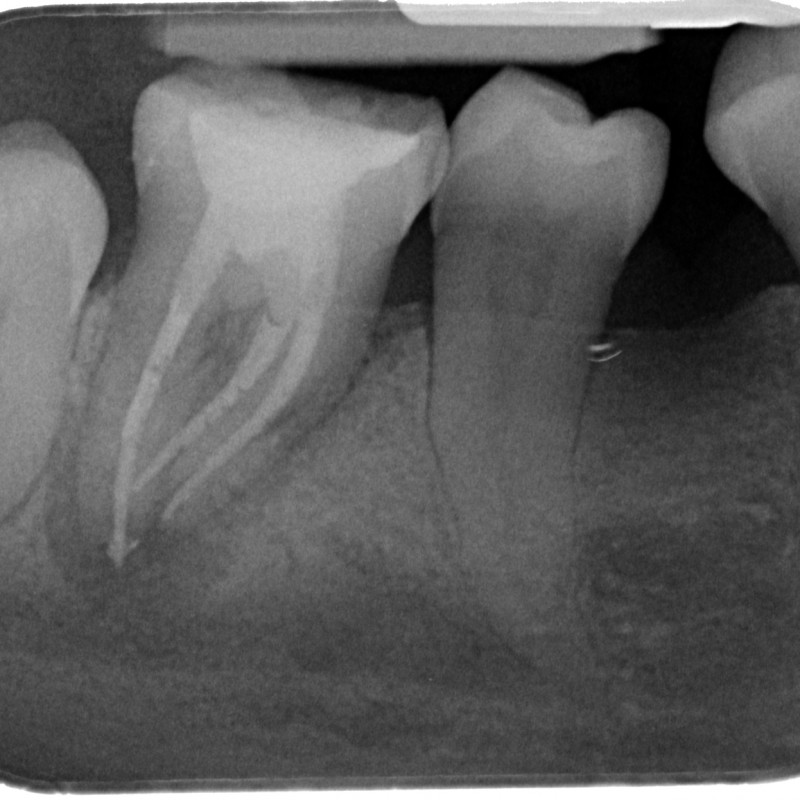

721106-07-5220-X-20150521-145313-XCSP0ZO8VCHE-3